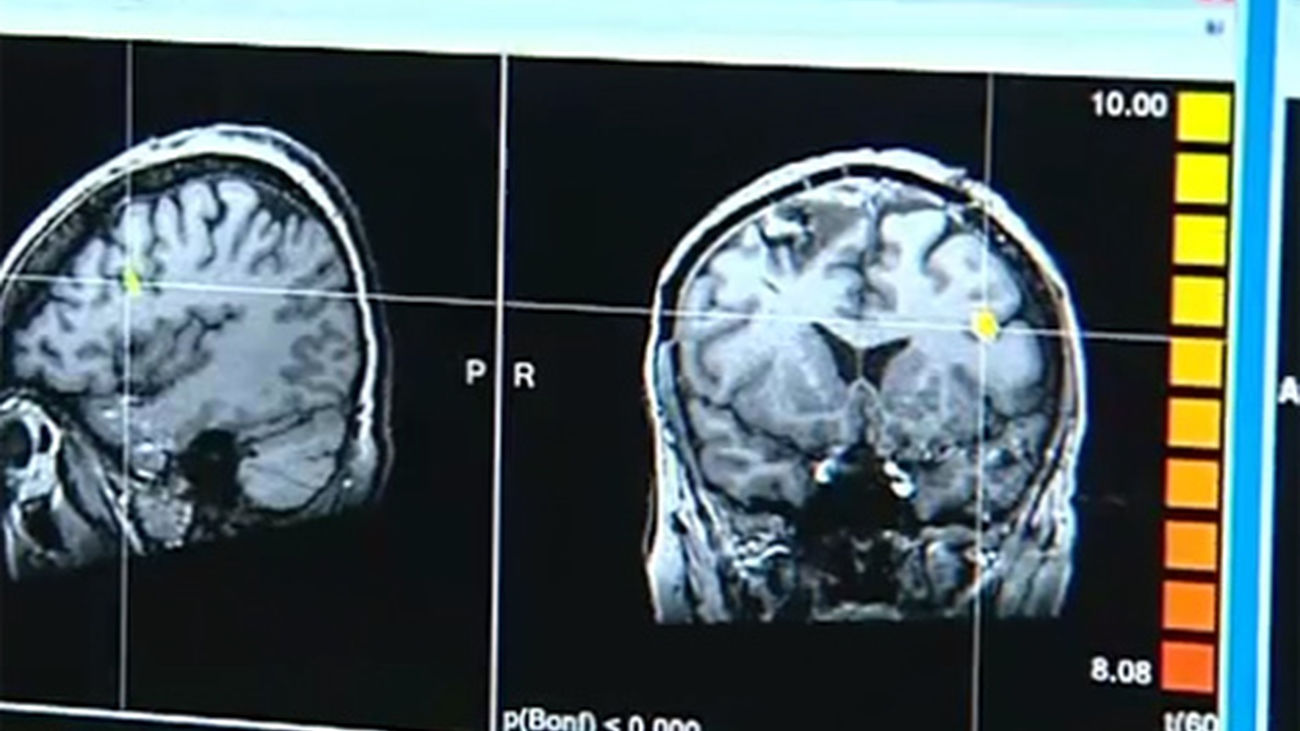

Cada año 11.000 madrileños sufren un ictus

La principal causa de daño cerebral es el ictus, al que le corresponden 99.284 de estos casos anuales, seguido por el traumatismo craneoencefálico (4.938 casos anuales) y la anoxia (1.442 casos anuales). Esta alta incidencia del ictus se ve reflejada en los datos de prevalencia, ya que un 78 por ciento de las 420.000 personas con daño cerebral lo desarrollaron a causa de un accidente cerebrovascular.